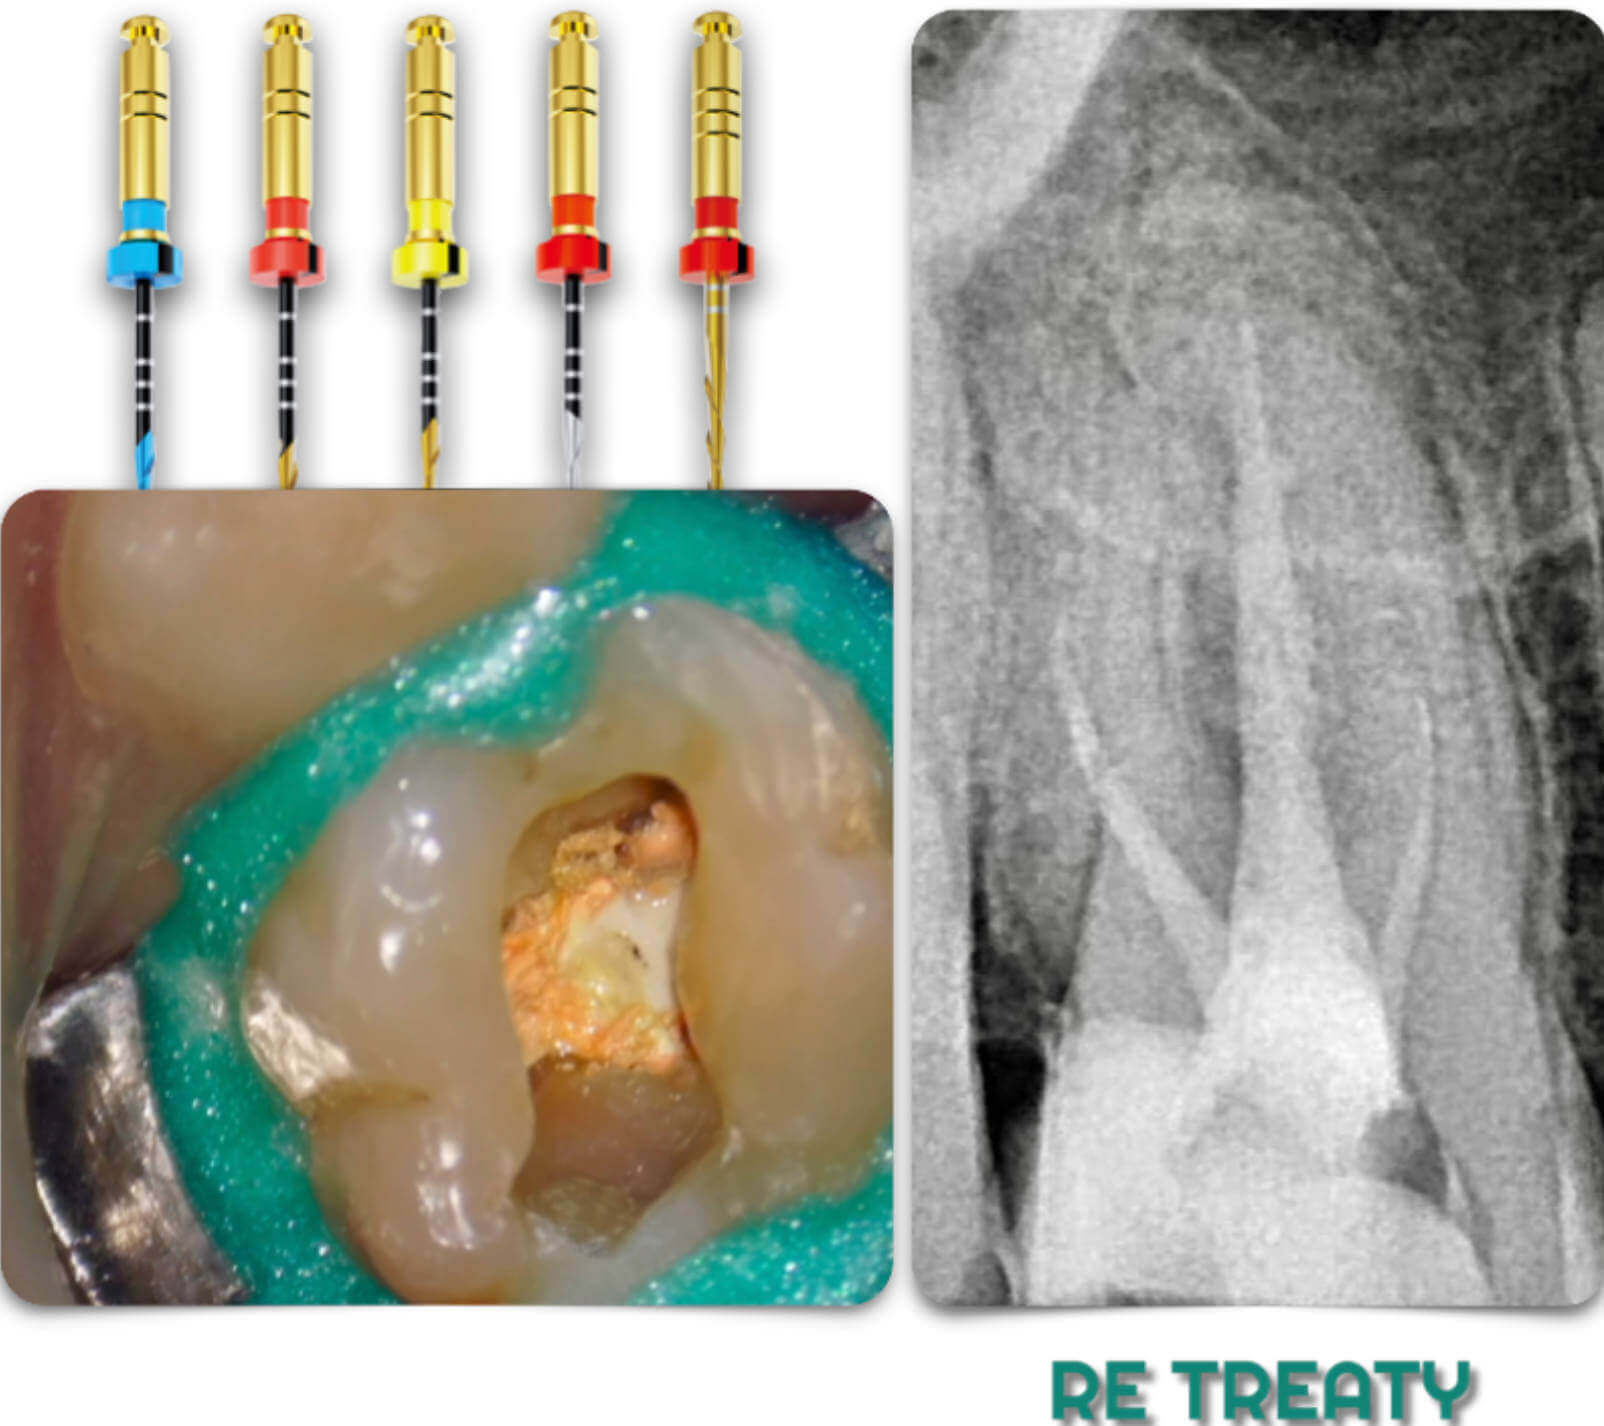

In this article we are introducing the RE-TREATY files for the retreatment of Maxillary Molar and we will show how the system combines the function of Cutting Efficiency & Flexibility to facilitate the Retreatment step in a conservative way.

Fig. 1

The Pre - Op Radiograph shows a Maxillary Molar DB ledge & Short filling in all the roots.

Five conservative highly effective instruments were used in sequence .

BULLY

SKINNY

SHAPY 1 ,2 & 3